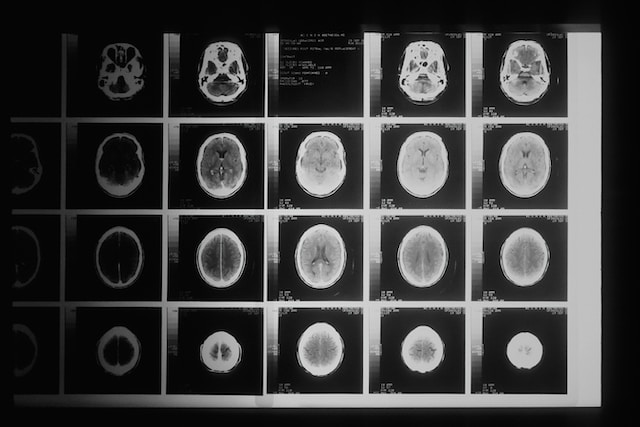

TAC

La tomografía Axial computarizada (TAC) es un procedimiento diagnóstico que, mediante la emisión de rayos X, permite obtener cortes muy finos de una determinada parte del cuerpo con elevada resolución. El TAC es una técnica rápida que ofrece imágenes de máxima resolución, permite la detección de múltiples tumores en fases tempranas y en su seguimiento. Además, es la técnica de elección en las enfermedades pulmonares y del tubo digestivo.

TAC de Cabeza o Cuello

Una prueba de diagnóstico por imagen ideal para evaluar estructuras de cabeza y cuello, como glándulas salivales, cavum, vasos sanguíneos y más.

¿QUÉ ES EL TAC?

La tomografía axial computarizada (TAC o TC) es una prueba de diagnóstico médico que utiliza una fuente motorizada de rayos X (gantry) con un mecanismo giratorio al rededor del paciente, lo que permite obtener cortes de imágenes detallados del interior del cuerpo.

Las imágenes obtenidas en un TAC tienen una mucho mayor resolución y capacidad diagnóstica en comparación con una radiografía tradicional. Además, con esta técnica se eliminan las estructuras superpuestas, haciendo que la anatomía interna sea más aparente.

Durante el procedimiento, la camilla irá avanzando a través de un tomógrafo, el cual tiene forma de dónut y rodea el perímetro del paciente. A medida que rotan los elementos emisores de los rayos X y los detectores, se mide la cantidad de radiación absorbida por los diferentes tejidos en todo el cuerpo. Esto es lo que permite la obtención de imágenes transversales o cortes. Cuando una máquina de computación coloca todos los cortes juntos, se obtiene una visualización multidimensional muy detallada del interior del organismo, lo que permite el diagnóstico de una amplia gama de condiciones y enfermedades.